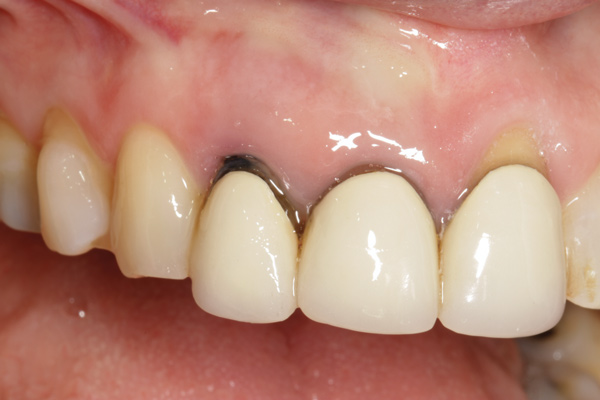

Fig 11. Four months after healing, a final crown was placed. An esthetically pleasing outcome was achieved.

Figure 11